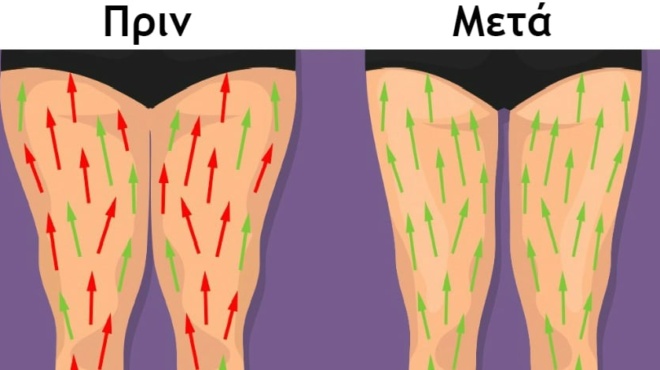

· Βάλτε ελαστικό επίδεσμο στην περιοχή του γονάτου μέχρι να υποχωρήσει το πρήξιμο. Μην σφίξετε πολύ τον επίδεσμο γιατί δε θα γίνεται καλή κυκλοφορία του αίματος.

· Όταν θα έχει φύγει το οίδημα κάντε ζεστές κομπρέσες για λίγες ημέρες προκειμένου να βελτιωθεί η ροή του αίματος αλλά και για πιο γρήγορη ανάρρωση.

· Συμπίεση – εάν χρησιμοποιείτε επίδεσμο/κάλτσα συμπίεσης στη διάρκεια της ημέρας μπορεί να περιοριστεί η δυσφορία που αισθάνεστε.

· Ύψωση – όταν αναπαύεστε σηκώστε το πόδι σας (με μαξιλάρια) πάνω από το ύψος της καρδιάς για να περιορίσετε το οίδημα.